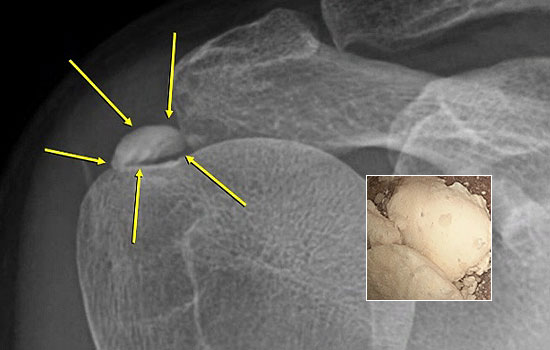

어깨의 석회는 그 시기에 따라 액체형과 고체형 그리고 혼합형으로 존재할 수 있습니다.

액체형 석회를 흡인하는 것은 어디에서나 가능합니다. 하지만 고체형 그리고 혼합형 제거에는 많은 노하우가 필요합니다.

서울거탑정형외과에서는 고체형 석회를 잘게 분쇄하여 뽑아내는 독자적인 기술과 노하우를 보유하고 있습니다.

형성기/휴지기의 고체형 석회

흡수기의 액체형 석회

해당 시술은 석회의 위치를 초음파로 정확히 확인한 뒤,정교한 기술로 진행되는 비수술 치료입니다.

그만큼 의료진의 숙련도와 경험이 매우 중요하므로, 풍부한 시술 경험을 가진 정형외과 전문의를 통해 치료받는 것이 좋습니다.

서울거탑정형외과에서는 풍부한 노하우로 초음파를 통해 정확히 석회를 확인 후 고체형일지라도 미세하게 분쇄하여 제거가 가능합니다.

95%이상 석회 제거가 가능합니다.